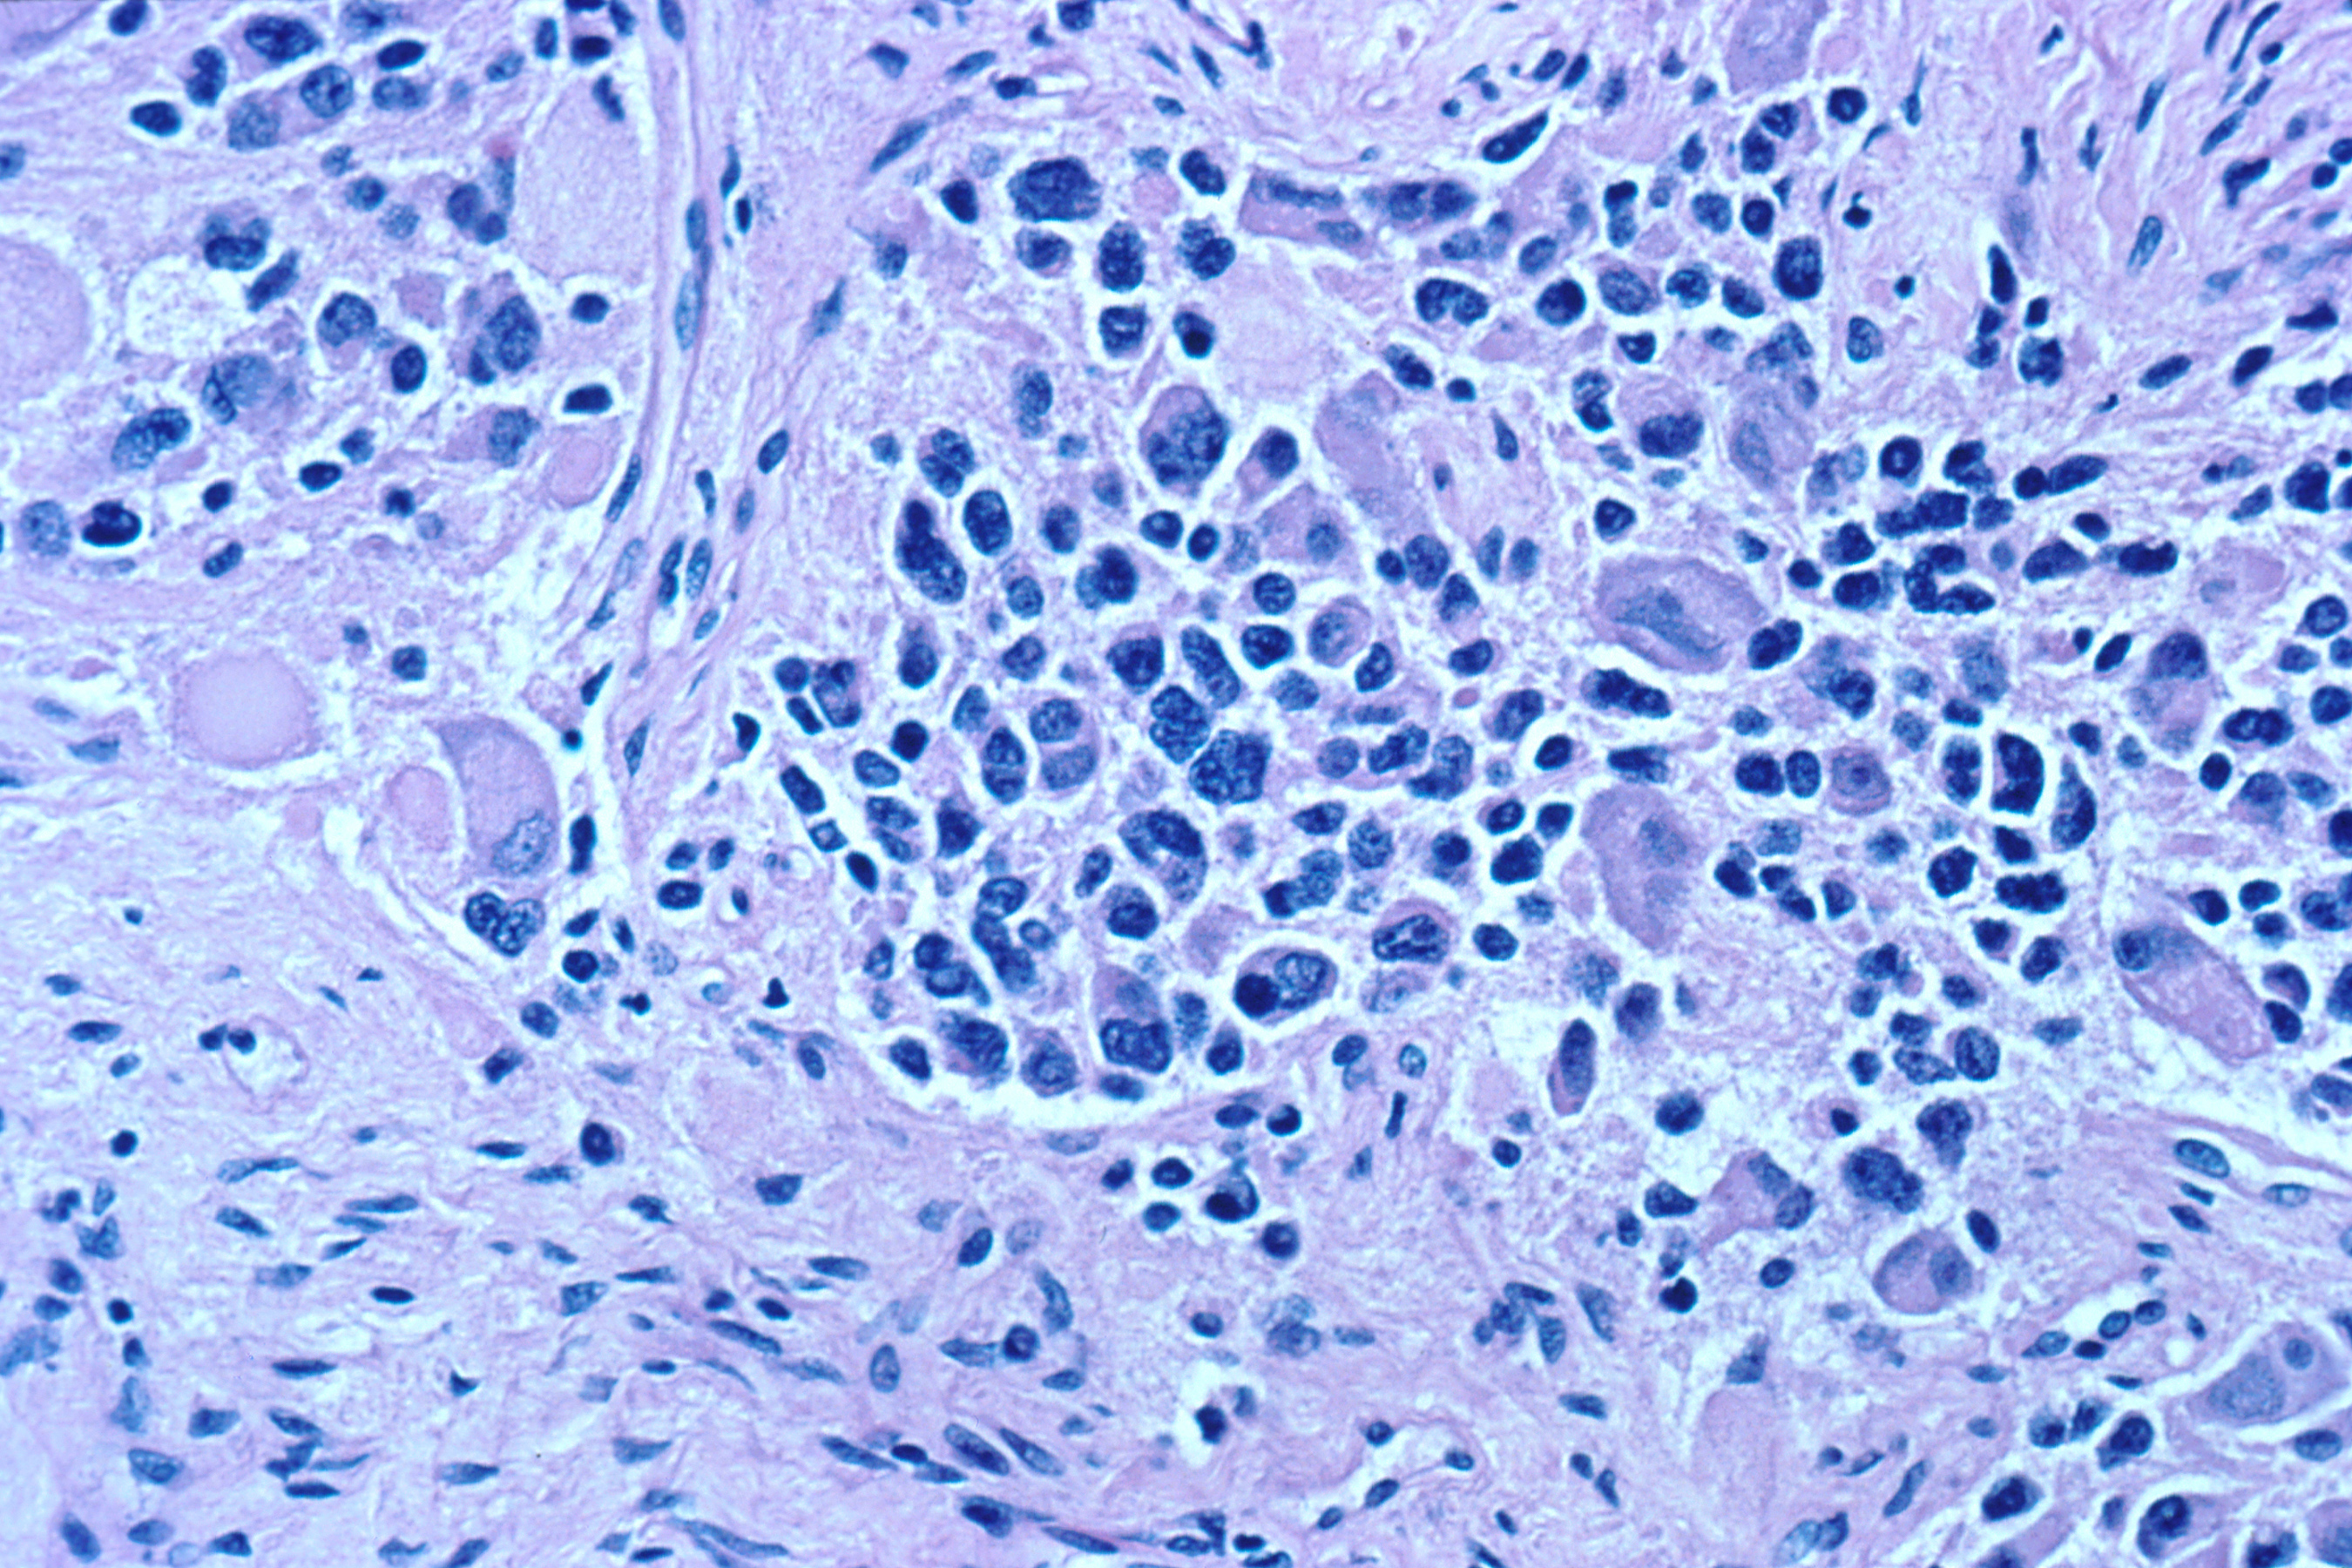

현미경 검사에서 종양 세포는 일반적으로 작고 둥글며 파란색으로 묘사되며, 로제트 패턴(호머 라이트 가성 로제트)이 보일 수 있다. 호머 라이트 가성 로제트는 신경총 주변의 종양 세포이며, 비어있는 내강 주변의 종양 세포인 진성 로제트와 혼동해서는 안 된다.[28] 또한, 교상 섬유 산성 단백질(GFAP) 양성 돌기가 혈관을 향해 가늘어지는 뇌실종(두 가지의 조합)으로 구성된 뇌실종의 가성 로제트와도 구별된다.[29] 병리학자들은 신경아세포종을 횡문근육종, 유잉 육종, 림프종 및 윌름스 종양과 같은 조직학적 모방체와 구별하기 위해 다양한 면역조직화학적 염색을 사용한다.[30]